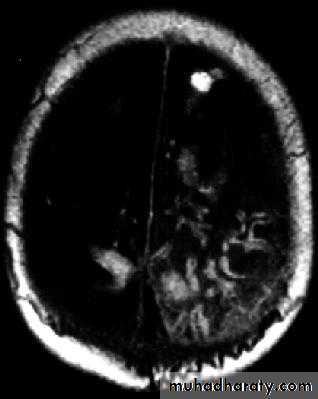

Brain Abscess MRI

• B. Radiological Investigations:• CT or MRI is the investigation of choice.

• CT Brain is performed with and without contrast.

• MRI is done with gadolinium enhancement.

• They will show a single (or multiple) space occupying lesion that is well delineated with an enhancing wall, with variable surrounding oedema.